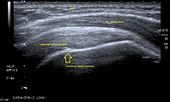

Transversal ultra sonography of the supraspinatus tendon

Ultrasound

There are several advantages of ultrasound. It is relatively cheap, does not emit any radiation, is accessible, is capable of visualizing tissue function in real time, and allows the performance of provocative maneuvers in order to replicate the patient’s pain.[25] Those benefits have helped ultrasound become a common initial choice for assessing tendons and soft tissues. Limitations include, for example, the high degree of operator dependence and the inability to define pathologies in bones. One also has to have an extensive anatomical knowledge of the examined region and keep an open mind to normal variations and artifacts created during the scan.[26]

After the introduction of high-frequency transducers in the mid-1980s, ultrasound has become a conventional tool for taking accurate and precise images of the shoulder to support diagnosis.[28][29][30][31][32]

Adequate for the examination are high-resolution, high-frequency transducers with a transmission frequency of 5, 7.5, and 10 MHz. To improve the focus on structures close to the skin an additional "water start-up length" is advisable. During the examination the patient is asked to be seated, the affected arm is then adducted and the elbow is bent to 90 degrees. Slow and cautious passive lateral and/or medial rotations have the effect of being able to visualize different sections of the shoulder. In order to also demonstrate those parts which are hidden under the acromion in the neutral position, a maximum medial rotation with hyperextension behind the back is required.[33]

To avoid the different tendon echogenicities caused by different instrument settings, Middleton compared the tendon’s echogenicity with that of the deltoid muscle, which is still lege artis.[34][35]

Usually the echogenicity compared to the deltoid muscle is homogeneous intensified without dorsal echo extinction. Variability with reduced or intensified[36] echo has also been found in healthy tendons. Bilateral comparison is very helpful when distinguishing and setting boundaries between physiological variants and a possible pathological finding. Degenerative changes at the rotator cuff often are found on both sides of the body.[37] Consequently, unilateral differences rather point to a pathological source and bilateral changes rather to a physiological variation.[35]

In addition, a dynamic examination can help to differentiate between an ultrasound artifact and a real pathology.[38]

To accurately evaluate the echogenicity of an ultrasound, one has to take into account the physical laws of reflection, absorption and dispersion. It is at all times important to acknowledge that the structures in the joint of the shoulder are not aligned in the transversal, coronal or sagittal plane, and that therefore during imaging of the shoulder the transducer head has to be held perpendicularly or parallel to the structures of interest. Otherwise the appearing echogenicity may not be evaluated.[39]